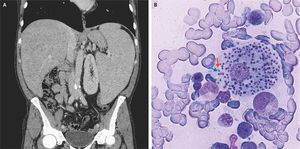

A 49-year-old previously healthy man presented to the emergency department with a 5-month history of fever, abdominal pain, fatigue, and an unintentional 15-kg weight loss. The physical examination was notable for an enlarged liver and spleen. Laboratory studies showed a white-cell count of 2040 per cubic millimeter (reference range, 4000 to 10,000), a hemoglobin level of 9.2 g per deciliter (reference range, 14.0 to 18.0), and a platelet count of 50,000 per cubic millimeter (reference range, 140,000 to 400,000). Blood cultures as well as tests for human immunodeficiency virus, hepatitis B virus, hepatitis C virus, cytomegalovirus, and Epstein–Barr virus were negative. Computed tomography of the abdomen confirmed the presence of an enlarged liver and markedly enlarged spleen (Panel A). Examination of a bone marrow aspirate revealed amastigotes, each with a nucleus (Panel B, blue arrow) and a kinetoplast (Panel B, red arrow), within histiocytes. This is the typical appearance of leishmaniasis, and polymerase-chain-reaction testing of the bone marrow aspirate confirmed the diagnosis. Transmitted by sandflies, Leishmania infantum is endemic to Italy and the Mediterranean region. The patient started treatment with liposomal amphotericin B. At a follow-up visit 1 month later, the fever, abdominal pain, and fatigue had resolved, and physical examination revealed resolution of the splenomegaly. Giuseppe G. Loscocco, M.D. Matteo Piccini, M.D. University of Florence, Florence, Italy